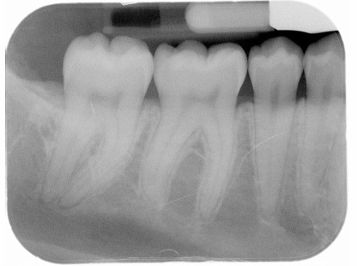

What is the problem with this UNDERDEVELOPED FILM X-ray?

Appears light, Inadequate development time, Developer solution too cool, Inaccurate timer or thermometer, Depleted or contaminated developer solution

How would you resolve this UNDERDEVELOPED FILM X-ray?

Check development time, Check developer temperature, Replace faulty time or thermometer, Replenish developer with fresh solutions as needed